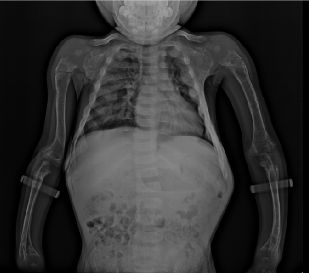

鸡胸(pectus carinatum)又称鸽胸。胸骨向前隆起畸形,状如鸡、鸽子之胸脯故称之为鸡胸,是前胸壁第二种常见的胸廓畸形,较漏斗胸少见,发病率约千分之一,男女比例约4:1,占所有胸壁畸形的16.7%。病因尚未明确,可能与遗传有关,有家族史者约20%~25%。一般认为是肋骨和肋软骨过度生长造成的,胸骨的畸形是继发于肋骨畸形的,也可继发于胸腔内疾病。。

王长江说,实际上,仅通过补钙并不能治疗鸡胸,这是一种误区。鸡胸是一种常见的胸廓畸形,表现为:胸骨向外异常突出,状如禽类的胸骨,也是“鸡胸”的由来。它和漏斗胸一样,属于常见的胸廓畸形。以往认为鸡胸发病多与钙磷代谢有关,多由营养不良引起钙的摄入不够或吸收障碍引起,因此很多人采取补钙治疗。但近些年研究发现,鸡胸的主要原因是肋骨和肋软骨过度生长造成的,变长的肋软骨向前凸起形成鸡胸,向后凹陷形成漏斗胸,必须通过微创手术才能有效矫正鸡胸病。